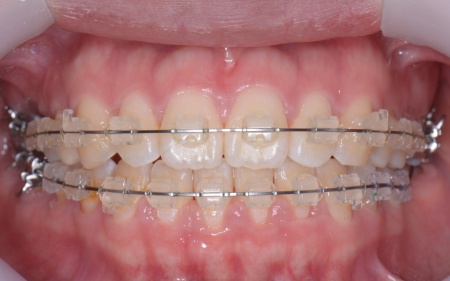

| カウンセリング | 拝見したところ、右上と左下の奥歯に強い痛みが出ていました。 レントゲンで確認した結果、どちらも歯の根が割れていることが判明しました。 歯の根が割れたまま放置すると噛むときの痛みが続くだけでなく、炎症が広がって周囲の歯や骨にまで影響を及ぼすおそれがあります。 また、上下の歯を噛み合わせた際に前歯が噛み合わず隙間ができる開咬(かいこう)と呼ばれる噛み合わせも見られました。 以上のことから、抜歯後に歯を補う治療と噛み合わせを改善するための治療が必要と診断しました。 |

患者様は「健康な歯をできるだけ守りたい」との理由から、③のインプラント治療を希望されました。 まず、右上と左下の奥歯を抜歯しました。 矯正がある程度進んだ段階で、右上と左下のインプラント手術を実施しました。 インプラント手術後は矯正治療の仕上げを行い、装置を外しています。 治療終了後、下前歯の間に見られる三角形のすき間(ブラックトライアングル)が気になるとのご相談がありました。 |